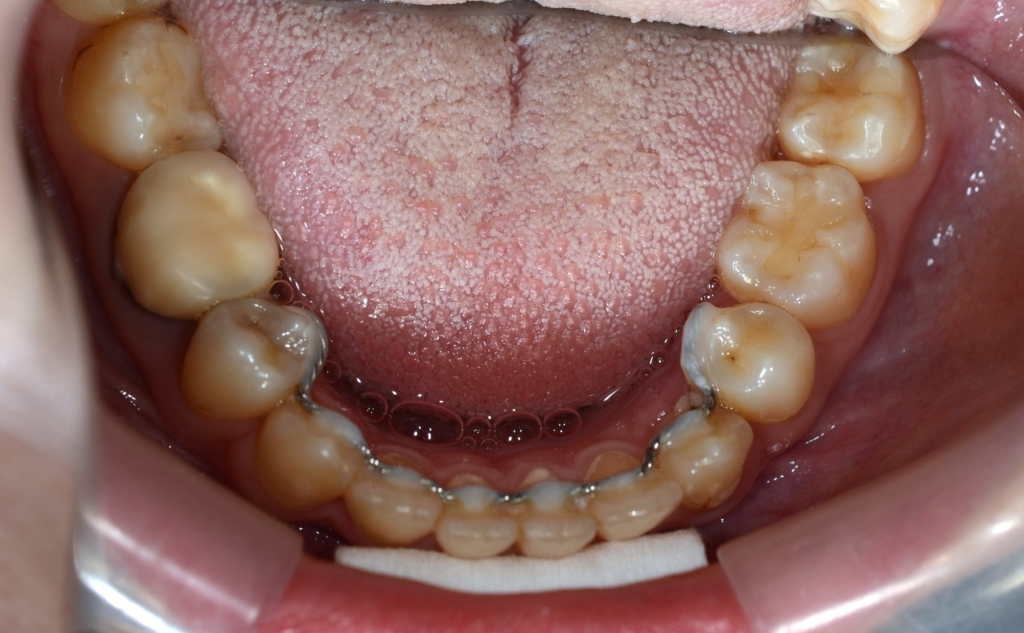

ついでに、歯並びの比較です

上段が矯正治療前、下段が矯正治療後